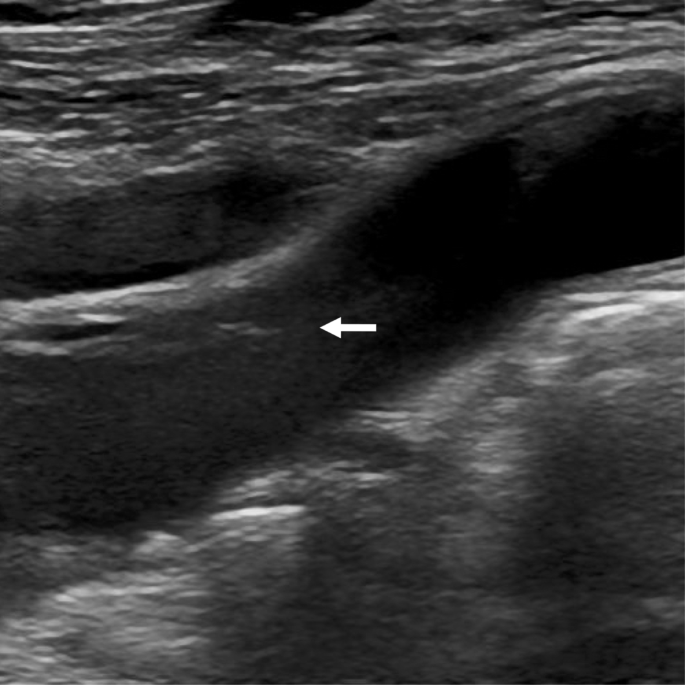

一名64岁的女性患者患有EGPA,并出现霍纳综合征(Horner syndrome)。她正在接受EGPA的糖皮质激素治疗以及心房颤动的抗凝治疗。超声检查显示颈总动脉和颈内动脉内存在内膜瓣和双腔结构。患者继续接受药物治疗,未发生缺血性中风,发病6个月后的随访显示霍纳综合征有所改善。超声检查未发现复发或动脉瘤形成,但颈动脉夹层是否完全愈合尚未得到确认。

一名64岁的女性患者因发现左眼视野异常而就诊。她有高血压、血脂异常、支气管哮喘、心房颤动、EGPA和胸主动脉夹层(TAD)以及白内障的病史。八年前,在调查多发性周围神经病变和中年发病的哮喘原因时,她发生了急性TAD并接受了紧急手术(主动脉移植)。随后被诊断为EGPA。她已经接受了14年的心房颤动抗凝治疗,并且也在接受EGPA的糖皮质激素治疗。眼科医生发现她的左眼视野异常,将其转诊至我们医院进行进一步检查。患者没有头痛、面部或颈部疼痛,也没有近期外伤史。体格检查显示她的左上眼睑轻度下垂(眼睑下垂),瞳孔缩小(瞳孔缩小,即霍纳综合征)。超声检查未发现复发或动脉瘤形成,但颈动脉夹层是否完全愈合尚未得到确认。

一名64岁的女性患者因约三周前发现左眼视野异常而就诊。她有高血压、血脂异常、支气管哮喘、心房颤动、EGPA和胸主动脉夹层(TAD)以及白内障的病史。八年前,在调查多发性周围神经病变和中年发病的哮喘原因时,她发生了急性TAD并接受了紧急手术(主动脉移植)。随后被诊断为EGPA。她已经接受了14年的心房颤动抗凝治疗,并且也在接受EGPA的糖皮质激素治疗。眼科医生发现她的左眼视野异常,将其转诊至我们医院进行进一步检查。患者没有头痛、面部或颈部疼痛,也没有近期外伤史。体格检查显示她的左上眼睑轻度下垂(眼睑下垂),瞳孔缩小(即霍纳综合征)。超声检查未发现复发或动脉瘤形成,但颈动脉夹层是否完全愈合尚未得到确认。